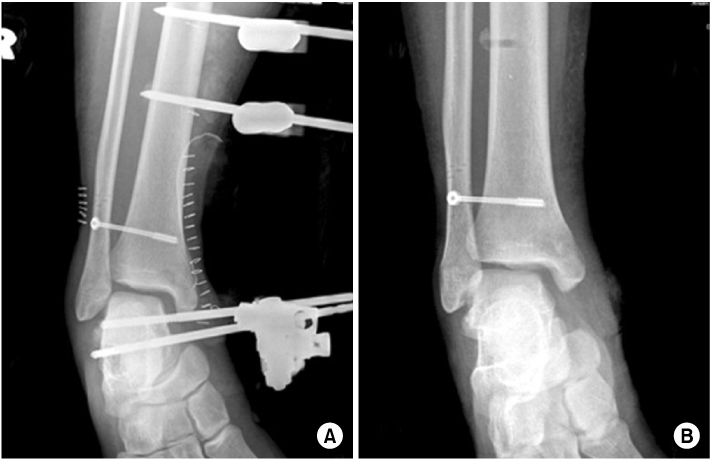

Fig. 3

Immediate post-traumatic radiographs of other clinic show that talus was displaced into distal tibiofibular space.

Fig. 3 Immediate post-traumatic radiographs of other clinic show that talus was displaced into distal tibiofibular space.